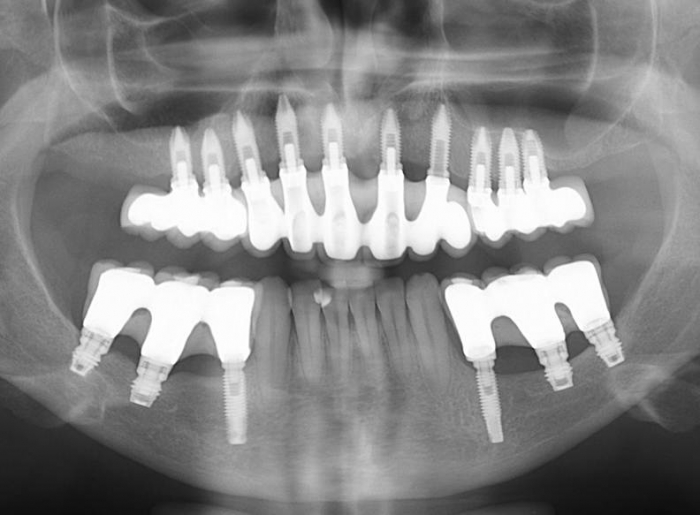

Raio X inicial